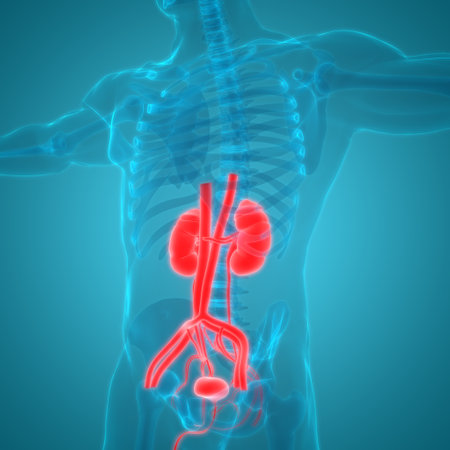

Human Urinary System Kidneys with Bladder Anatomy For Medical Concept 3D Illustration

3D Illustration Concept of Human Urinary System Kidneys with Bladder Anatomy

3D Illustration Concept of Human Urinary System Kidneys with Bladder Anatomy